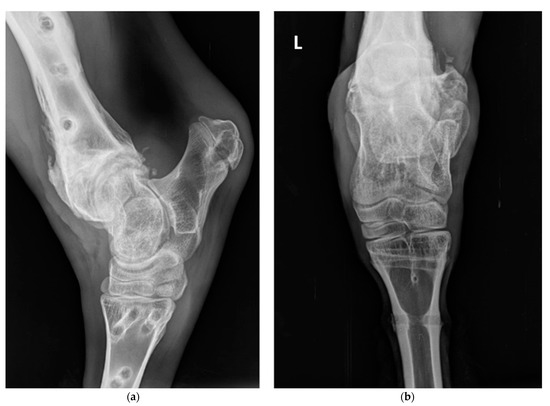

2. Case Presentation